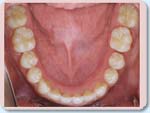

特に下の歯は内側に倒れこんだようになり(A3)、前歯はでこぼこしています。

治療後は前歯のかぶり具合は正常になり(B1)、上下の歯列もきれいなアーチ(円弧)をえがいています(B2,B3)。